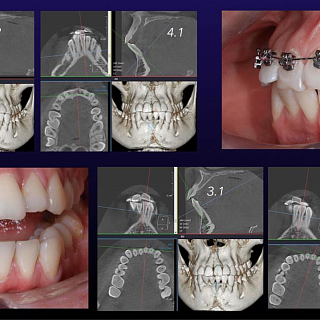

• ECR (External cervical resorption). Этиология цервикальной резорбции зуба. Классы ECR по G. Heithersay. Виды комплексной стоматологической помощи при различных классах цервикальной резорбции зубов. Тактика врача-ортодонта в разных возрастных периодах. Прогноз.EARR (External apical root resorption). Апикальная резорбция зуба. Эпидемиология. Стадии EARR по Malmgren. Этиология. Патофизиология. Молекулярно-генетические основы EARR. Тактика врача-ортодонта. Прогноз.

6. Анкилоз зубов. Этиология. Диагностика. Тактика врача-ортодонта у взрослого и растущего пациента при локализации анкилозированного зуба во фронтальном и боковом отделах.

7. Транспозиция зубов. Диагностика. Планирование ортодонтического лечения. Ошибки на этапе диагностики и реализации плана ортодонтического лечения.

8. Ретенция зубов. Ошибки и осложнения.